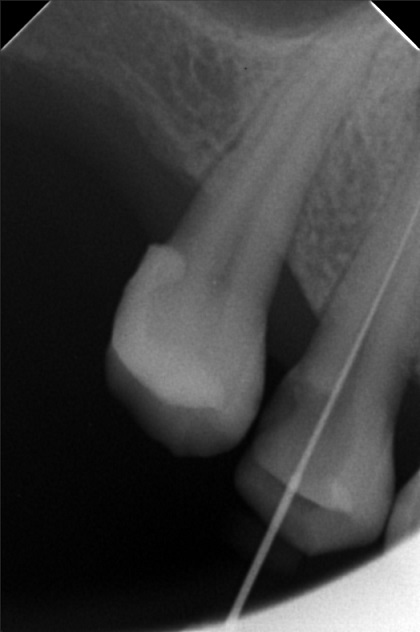

Edit Record Check our patient data records. Add patient information Patient Info Profile picture Last Name First Name Middle Name Birthdate Age Street Barangay City Country Zip Code Contact number Email Procedure 3/22/22- OP Lc 13 m/ 21 d/ 22 m/ 47 o/ b/ cervical xray 14 for rct 10/11/22 - OP (L); ACCESS #14, SCOUT #10 BL 18mm, EUGENOL. 10/14/22- 12/11/21/22- TF emax veneers 10/19/22 - 19mm, close w/ pulp devitalizer 09/02/23- op ** For change of crowns posterior Lower for Crown #15 08/13/24 OP 01/23/26 Alumina crwon #14 temporary crown OP Scanning File bangaros.jpg File 2 bongaros.jpg File 3 bongaros_02.jpg File 4 bongaros_03.jpg File 5 bongaros_04.jpg File 6 309497615_1081002115924778_349479569281481267_n.jpg File 7 bongaros_1.jpg File 8 bongaros_02_1.jpg File 9 File 10 File 11 File 12 File 13 File 14 File 15 File 16 File 17 File 18 File 19 File 20 Retain Record Retain Record Yes No Save Your Changes